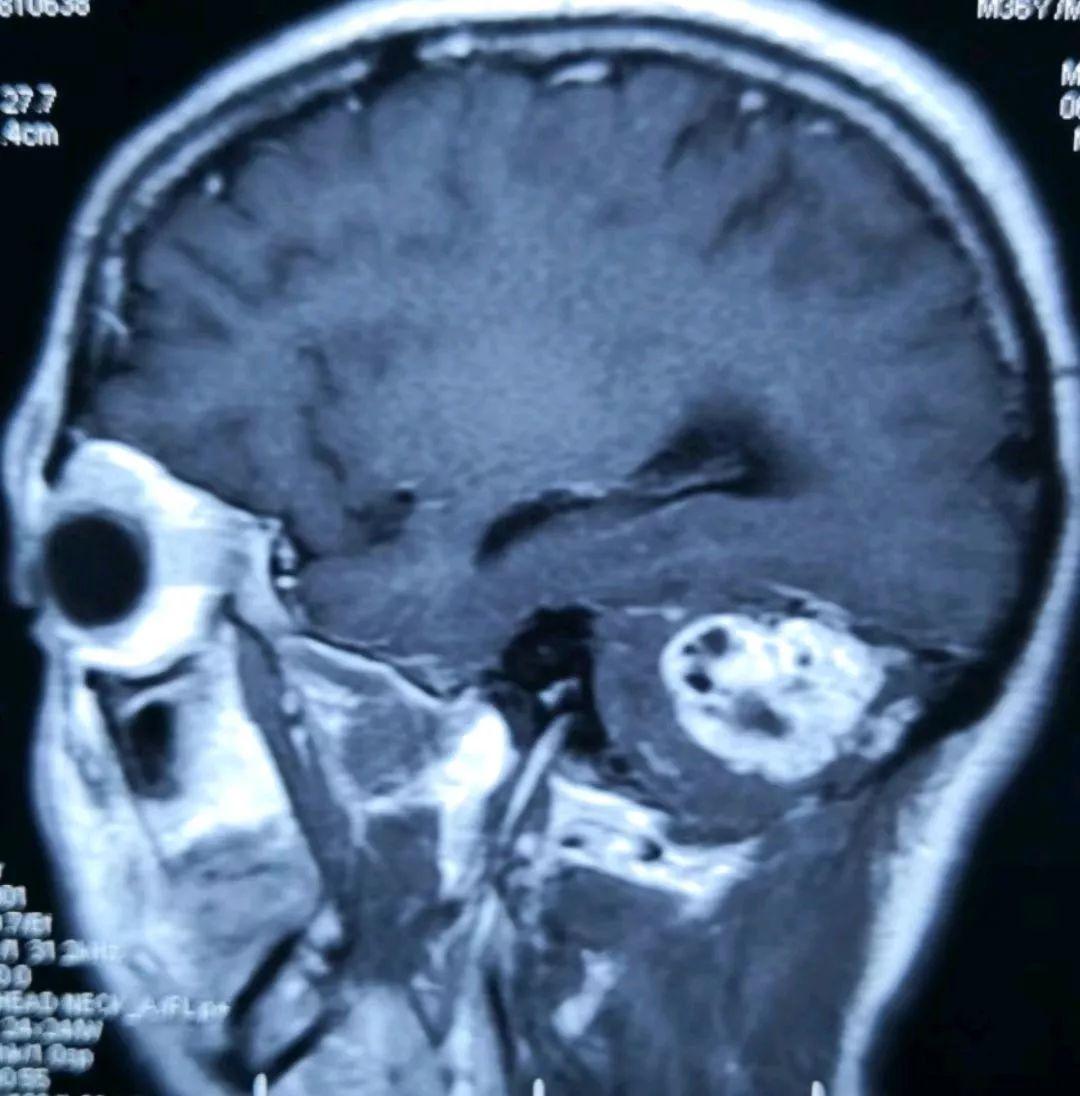

术前的磁共振片子提示右侧小脑半球的实质性血管母细胞瘤,增强显著(提示血供丰富)

另一位置的增强磁共振提示肿瘤长向小脑深部,靠近脑干组织(人的生命中枢)